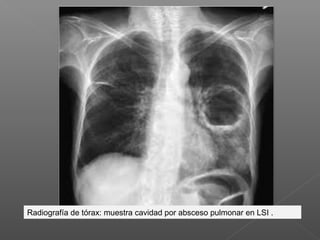

Radiografía de tórax: muestra cavidad por absceso pulmonar en LSI .

Radiografía de tórax:muestra cavidad por absceso pulmonar en LSI .